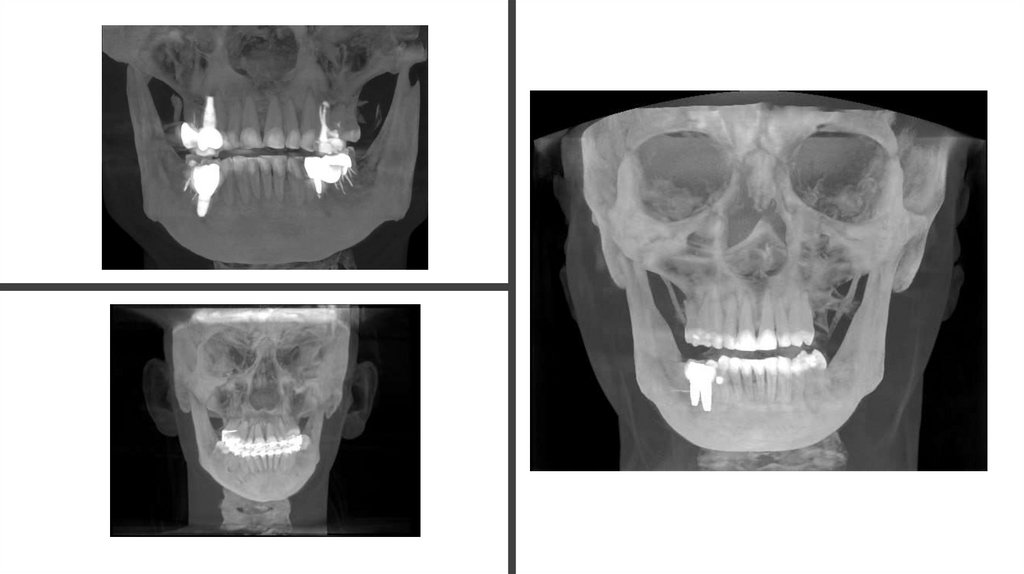

В этом исследовании мы исследовали потенциал моделей глубокого

обучения для автоматизации и улучшения анализа 3D-КЛКТ-сканирований с

помощью 2D-планарного вскрытия и панорамной реконструкции. Наша

сравнительная оценка YOLO, RetinaNet, Faster R-CNN и Mask R-CNN

показала, что YOLO превосходит другие в скорости и точности решения

этой задачи, что делает его наиболее эффективным выбором для

визуализации зубов в режиме реального времени.Технология U-образного

среза оказалась полезной для преобразования объемных данных в полезную

2D—аналитику, в то время как расширенная аналитика, включая кривые

обучения, тепловые карты обнаружения и сравнения с помощью радаров,

обеспечила строгую основу для оценки производительности моделей.

Несмотря на такие проблемы, как сложность аннотаций и вычислительные

затраты, эта работа подчеркивает жизнеспособность автоматизации на

основе искусственного интеллекта в клинических рабочих процессах,

сокращая ручные усилия и повышая точность диагностики.